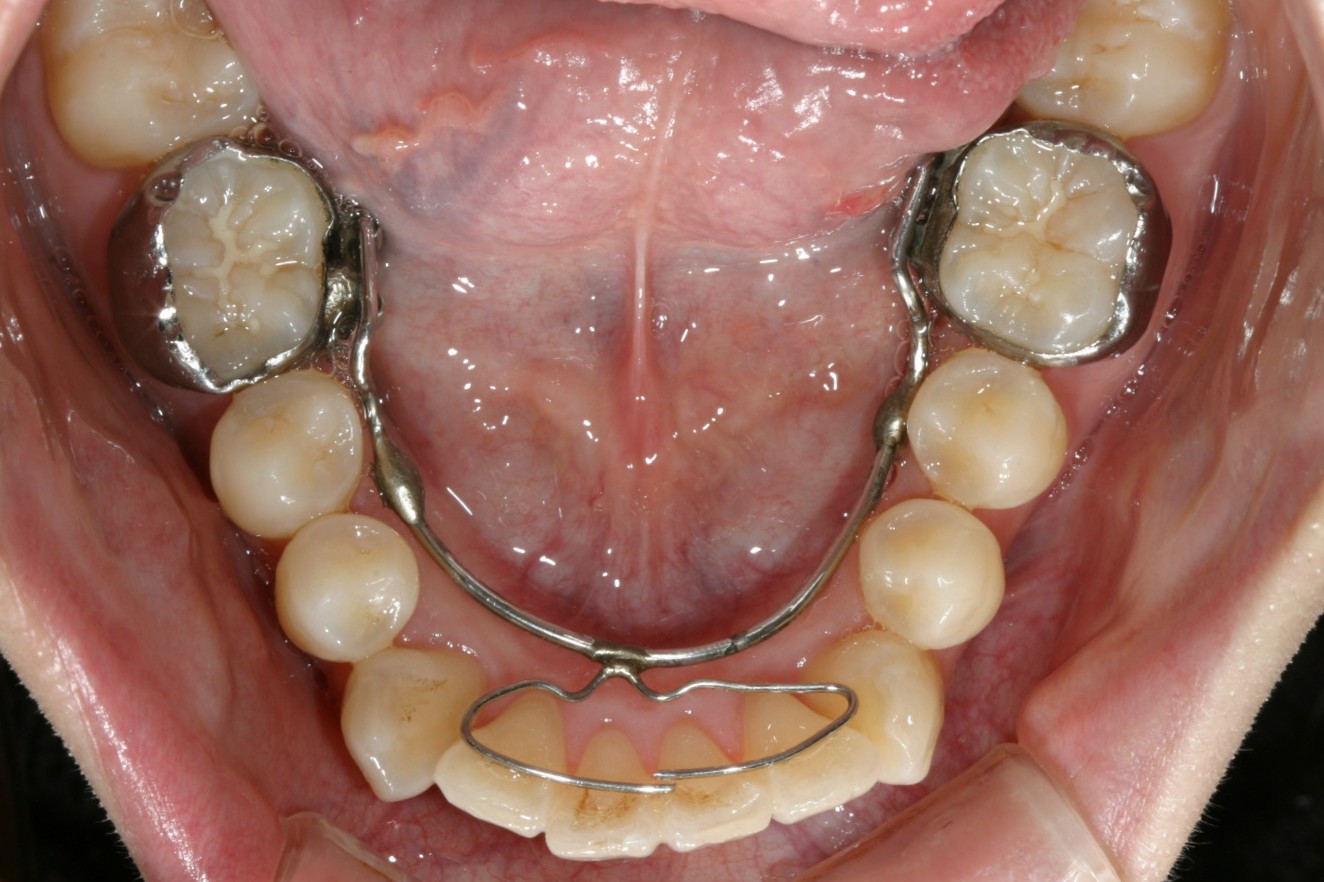

下顎にもリンガルアーチにてアーチ拡大と前歯の叢生治療です。

下顎もリンガルアーチ後インビザラインで治療を行いました。